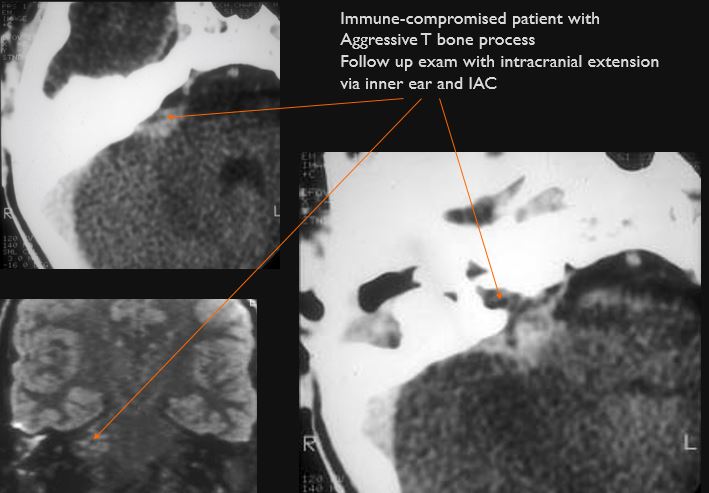

The inner ear, in particular the lateral semicircular canal and the cochlea are eroded or otherwise abnormal. [Yes/No]

There is dural reactive or leptomeningeal enhancement involving the internal auditory canal and the 7th and 8th cranial nerves. [Yes/No]